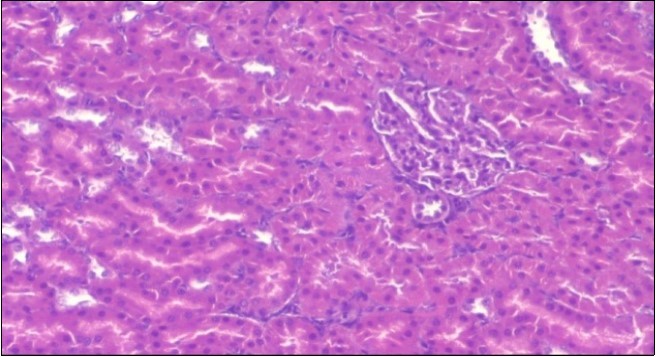

The histological examination of the kidney of the control rats fed on a standard diet showing normal rounded capsules with normal Bowman's glomeruli, round proximal tubules and elongated distal tubules with high cuboidal cells figure 1. The rats fed (HFD) showed fatty degeneration of the tubules with eosinophilic material deposition, glomerular atrophy with wide urinary space and distal tubules with extrusion of nuclei into lumen figure 2. By comparison kidneys of rats which were treated by fennel after being obese and the control rats observed partial improvement in both Bowman's capsules and proximal tubules. Note the distal tubules show less focal fatty infiltration figure 3.While examination of rats kidney that were treated by ator after obesity showed improvement in Bowman's capsules with normal glomerular and partial improvement in proximal tubules and distal tubules, figure 4. Kidney of rats that were treated by fennel and ator after obesity and the control rats showed high improvement in the tissues with normal glomerular and that Most of Bowman's capsules and renal tubules, restoring their normal appearance figure 5.

Figure 1.Photomicrogragh of kidney section of control rat showing normal rounded capsules with normal Bowman,s glomeruli, round proximal tubules and elongated distal tubules with high cuboidal cells , (H&E) (40X).